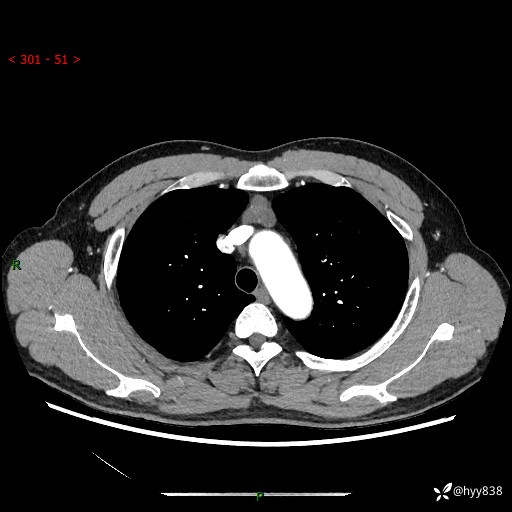

患者性别:女

患者年龄:49岁

简要病史:跟骨骨折,常规CT发现纵隔占位

胸部CT平扫

增强(动脉期+静脉期)